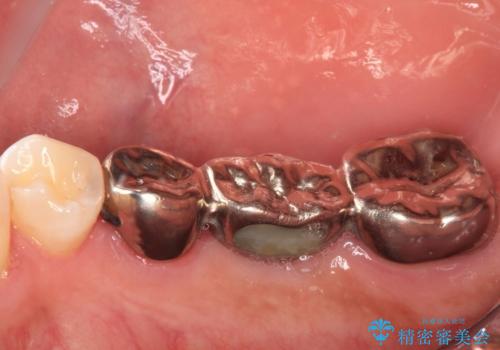

- 以前他院にて、保険診療で治療した金属のブリッジをやり替え希望の患者様です。

奥歯であっても、大きく笑うと金属色が目立ちます。

金属ブリッジを除去し、虫歯を完全に除去し、形を整え、

精度の高いシリコーン材料にて型どりをしました。